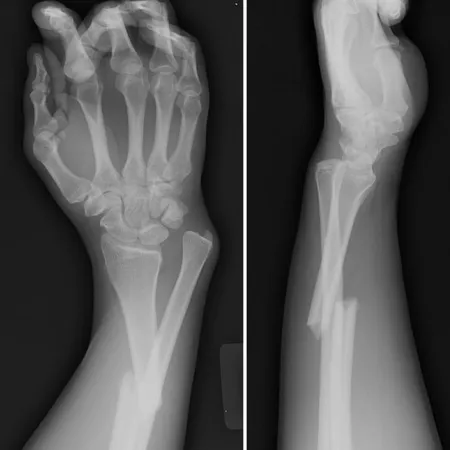

Broken Bone! เมื่อเจ้าตัวดีกระดูกหัก ร่างกายน้อยๆ ของเจ้าตัวเล็กมักมีความเสี่ยงที่จะได้รับอันตรายจากอุบัติเหตุอยู่บ่อยๆ ทั้งนี้เป็นเพราะหนูน้อยมักจะสนุกจนลืม...